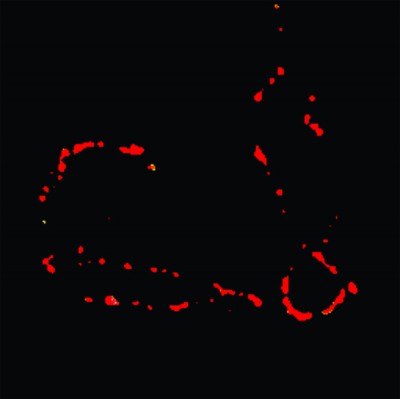

Científicos Argentinos desarrollan sensores fluorescentes para visualizar partículas nanométricas

Los científicos de la Facultad de Ciencias Exactas y Naturales de la UBA creen que, en el futuro, esta estrategia de microscopía podría usarse para la detección precoz del cáncer y otras enfermedades. Imagen...